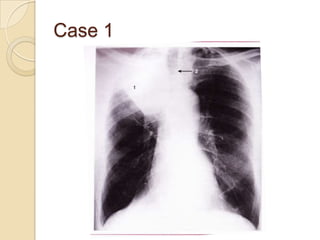

Case 1

   Right upper lobe

collapse

◦ Shadowing in upper

zone of right lung (1)

◦ Horizontal fissure is

elevated

◦ Tracheal deviation

towards the right (2)

◦ Ribs over

shadowing are

closer together than

normal

Case 1  Right upper lobe collapse ◦ Shadowing in upper zone of right lung (1) ◦ Horizontal fissure is elevated ◦ Tracheal deviation towards the right (2) ◦ Ribs over shadowing are closer together than normal